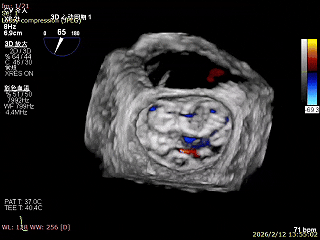

二尖瓣三维视图

2区彩色血流